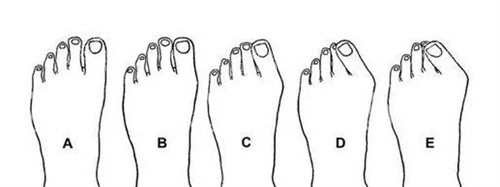

第四个原因:力线没调对,走路 “用错劲儿”

拇外翻手术的关键是把脚趾的力线调正,要是术后力线没调好,比如脚趾还是有点歪,走路时受力就会不均匀。

自查方法:光脚站在镜子前,看看手术的脚趾是不是跟其他脚趾在一条直线上,有没有往外侧歪 —— 要是明显歪着,可能是力线的问题。